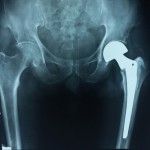

Case Study, Hip fracture, #AAOS Evidence Based Practice Guidelines

Popular answer may not imply right answer, Follow our twitter handle for the right answer, www.twitter.com/drhiteshg